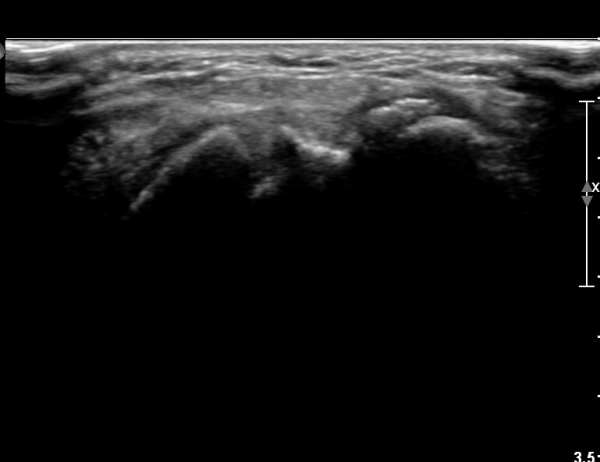

¼Õ¸ñ ¹èÃà, ̫̿ Á¾´Ü¸é°Ë»ç¿¡¼­ ô°ñ¼ö±Ù°ñ °üÀý³» ¼ö¾×Àú·ù¿Í »ï°¢°ñ Ç¥Ãþ¿¡ °ñ±ØÀÌ °üÂûµÈ´Ù(»çÁø 1),